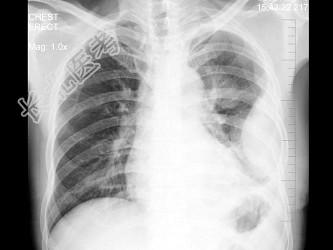

- 单项选择题如图所示,左侧胸部病变, 最可能的诊断为 ( )

A、包裹性积液

B、恶性胸膜间皮瘤

C、左下肺脓肿

D、左下肺癌

E、左侧胸腔积液